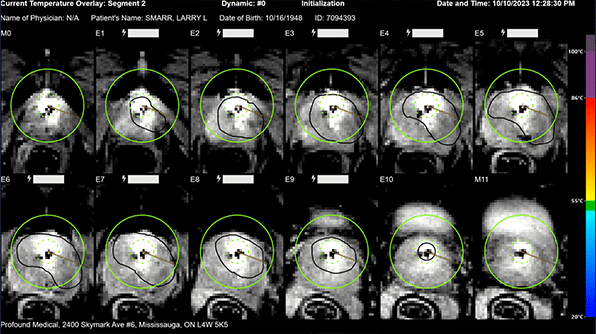

Invited Seminar Carl R. Woese Institute for Genomic Biology (IGB) University of Illinois, Urbana-Champaign May 10, 2024Larry Smarr’s Prostate Cancer Early Detection and Focal Therapy – Focus on Post-Therapy Time Series

UCLA Health IDx Abdominal Research Interest Group Meeting January 16, 2024Larry Smarr’s Prostate Cancer Early Detection and Focal Therapy